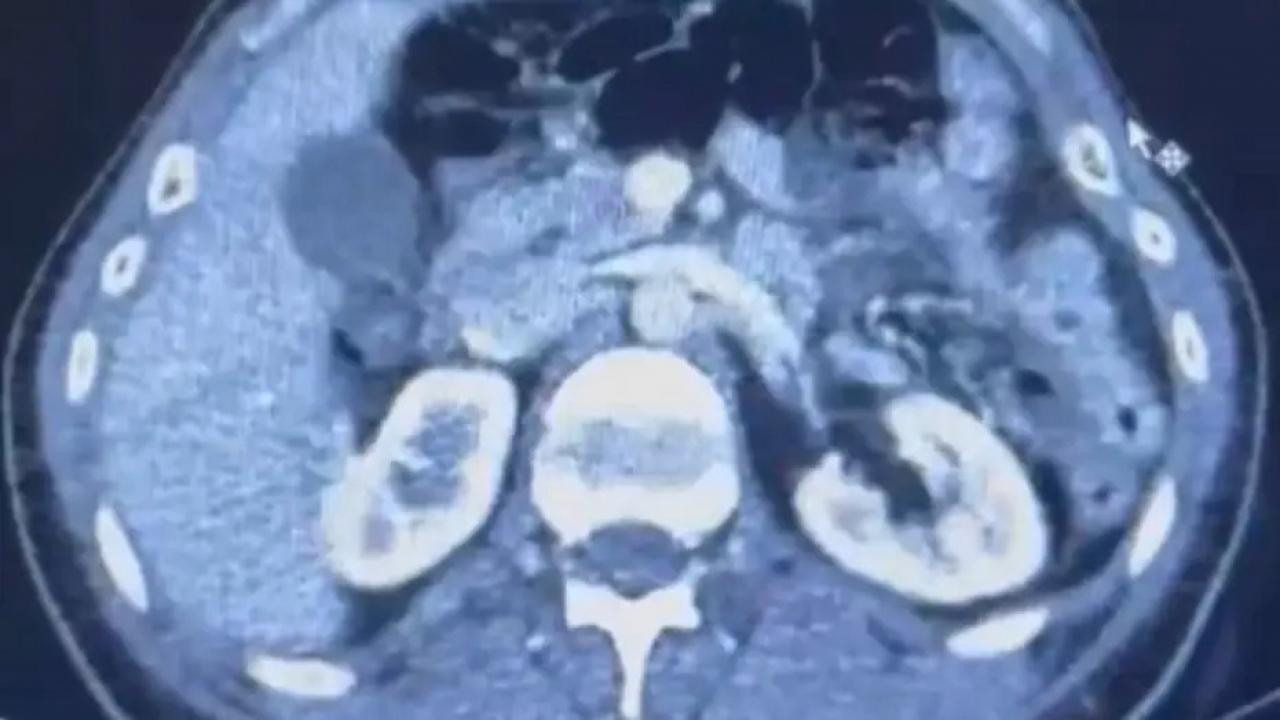

Şüphelilerden S.C. ve R.B.C. muayene edilmek üzere Kayseri Şehir Hastanesi'ne getirildi.

Röntgeni ve ultrason çekilen şüphelilerin midesinde yaklaşık 50 kapsülde 554 gram uyuşturucu olduğu tespit edildi.